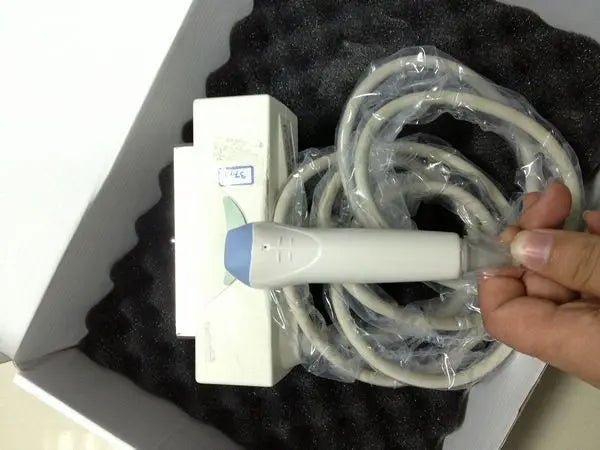

GE 3S Ultrasound Probe / Transducer Demo condition

Sale price$ 13,903.90